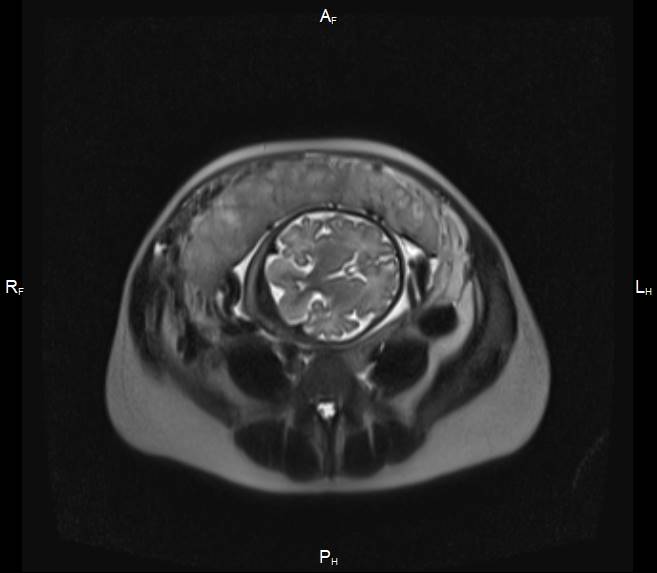

Первичный, или «материнский» этап, длительностью 3–5 минут, при котором получаемые Т2-ВИ многоплоскостные ортогональные МР-изображения (рисунок 1) ориентируются согласно анатомии беременной; целью его является оценка сегментарного расположения плацентарного диска в полости матки, контуров и размеров матки.

| Рисунок 1 – Беременность 36 нед. МРТ плаценты. Первичный, «материнский» этап исследования. Т2 ВИ в сагиттальной (а), корональной (б) и аксиальной (в) плоскостях | ||